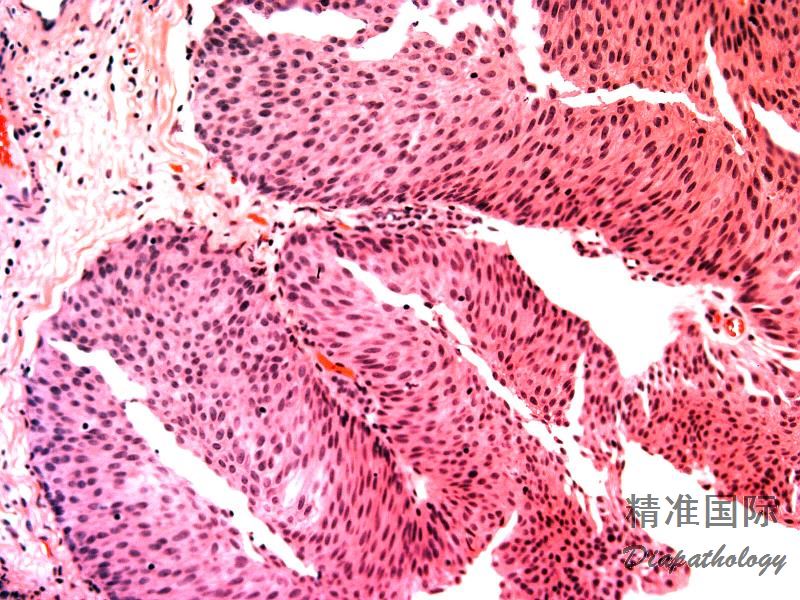

非浸润性低级别尿路上皮乳头状癌由纤细的乳头状结构组成,常见乳头分支和融合,被覆上皮层次增加。核轻度增大,可见空泡状染色质,常见核仁,核分裂可见于上皮的任何层次

镜下肿瘤由纤细的乳头状结构组成,常见乳头分支和融合,被覆上皮层次增加,极向较紊乱,至少局部存在不同程度的结构和细胞的异常。存在低倍镜下即可感知的细胞的非典型性,包括存在细胞极向,核大小,形状和染色质纹理的差异。

核轻度增大,可见空泡状染色质,常见核仁,核分裂可见于上皮的任何层次,但多位于基底部;

- 无间质浸润。